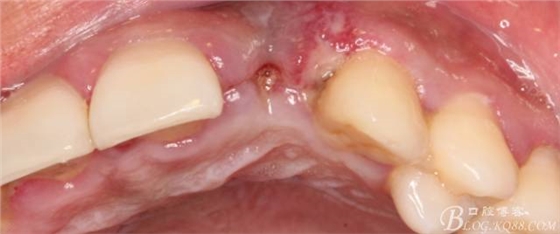

10天拆線一切正常,又過了兩周患者復(fù)診,自述期間無異常??趦?nèi)檢查,真的嚇了一跳,唇側(cè)鼓了個包,擠壓有白色分泌物溢出,絕對不是膿液,液體排除后,術(shù)區(qū)觸診空虛,外觀塌陷。這時候考研大夫的時刻到了,是先觀察一段時間再說?還是馬上進(jìn)行處理?我的回答是:馬上處理!如果你沒有及時處理,而是放患者回家觀察,那么接下來會發(fā)生如下情況:1.回家后患者家屬及親友會有很多你可以想象得到的討論;2.患者及家屬會對你產(chǎn)生不信任,勢必會到其他門診或醫(yī)院檢查,他院大夫會不會發(fā)表對你不利的言論;3甚至?xí)蚁嚓P(guān)法律界人士找你討要說法。

于是我果斷告知患者,手術(shù)失敗了,不能拖延,如不及時處理,炎癥繼續(xù)發(fā)展會很快波及鄰牙牙槽骨。患者接受我的建議。切開翻瓣,骨粉及生物膜消失了,骨吸收嚴(yán)重,幸運的是,因為處理及時,鄰牙骨支持依然存在。